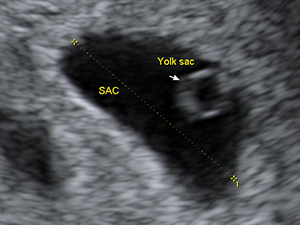

Gestational sac and yolk sac at 6 weeks